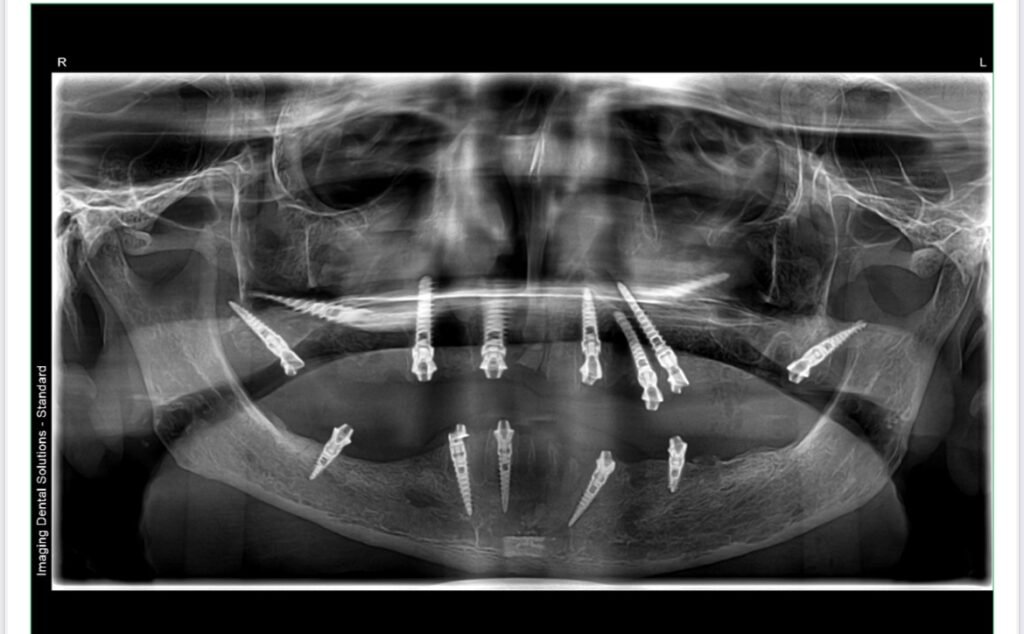

At Urban Smile Orthodontics & Dental Implants Centre, we are committed to transforming lives through advanced dental implant solutions. One of our recent success stories is a full-mouth restoration using immediate loading implants (I-Implants from Bioline), completed in just 5 days.

Our patient, a middle-aged individual suffering from severe tooth loss and compromised chewing ability, came to us looking for a permanent, aesthetic, and functional solution. After a thorough assessment, we recommended immediate loading full-mouth implants with screw-retained prosthetics—a superior alternative to conventional basal implants.

✔ Day 1: Comprehensive consultation, CBCT scan, and digital treatment planning.

✔ Day 2: Extraction of remaining hopeless teeth (if any) and strategic placement of Bioline I-Implants for full-mouth rehabilitation.